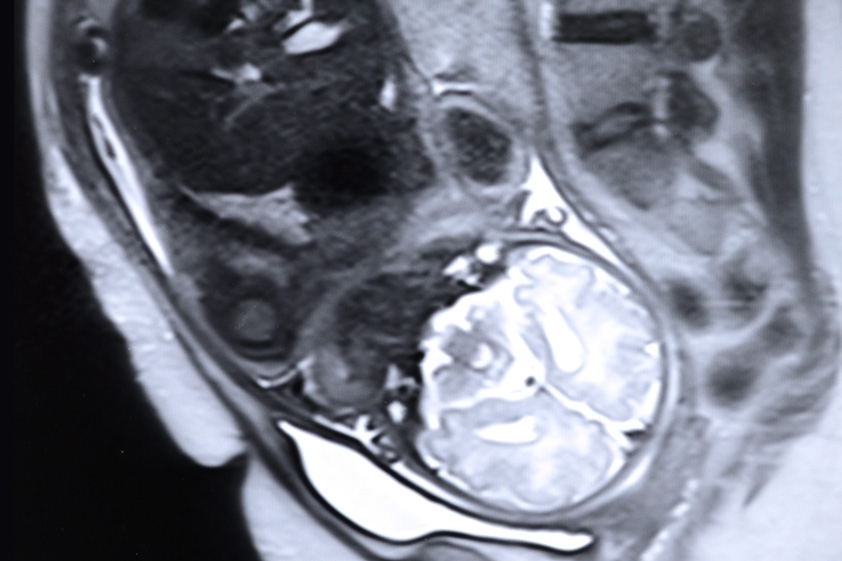

Caption: A team led by Polina Golland’s group at MIT’s Computer Science and Artificial Intelligence Laboratory has made a new algorithm for identifying organs in fetal MRI scans, which should make MRI monitoring much more useful. Pictured is a stock image of a fetal MRI.

A team led by Polina Golland’s group at MIT’s Computer Science and Artificial Intelligence Laboratory has made a new algorithm for identifying organs in fetal MRI scans, which should make MRI monitoring much more useful. Pictured is a stock image of a fetal MRI.